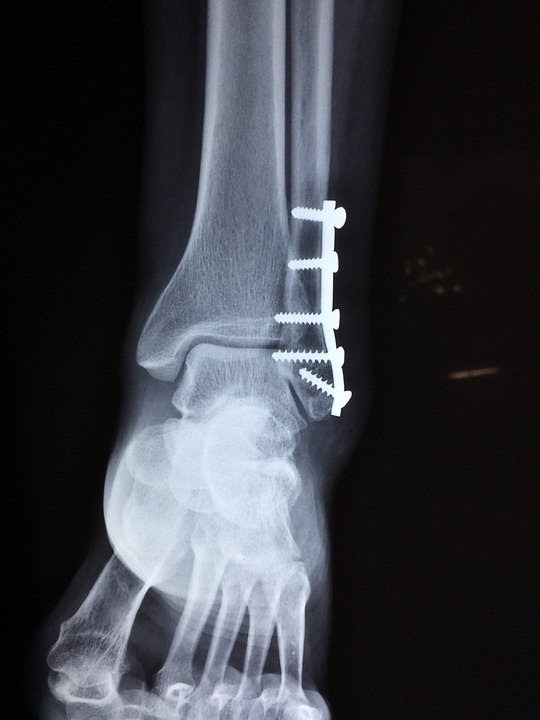

컴퓨터를 오랫동안 사용할 때 생기는 손목터널 증후군은 많은 사람들이 알고 있지만 발목터널 증후군에 대해서는 아는 분들이 별로 없습니다. 발목터널 증후군이란 정강이뼈의 신경이 끼어 감각에 이상이 생기는 질환입니다. 발목뼈가 부러지거나 금이 가서 거기서 나온 작은 조각들이 신경을 침범하여 생기는 것입니다.

여기서 오는 염증이 압박을 주게 돼서 생기기도 합니다. 보통 이 질환에 걸리면 발이 타는 듯한 통증이 나타나거나 오랜 시간 지속이 되면 감각이 떨어져 종아리까지 통증이 느껴질 수 있습니다.